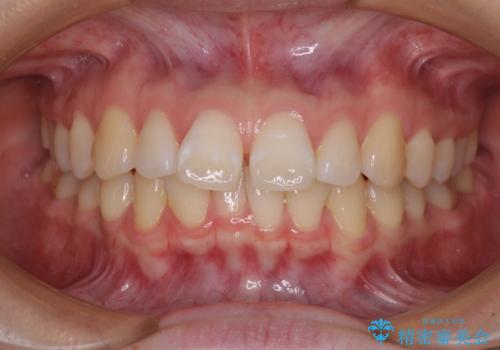

矯正歯科治療 → 叢生(でこぼこ・八重歯)

『目立たない装置で前歯のガタガタを治したい』インビザライン症例